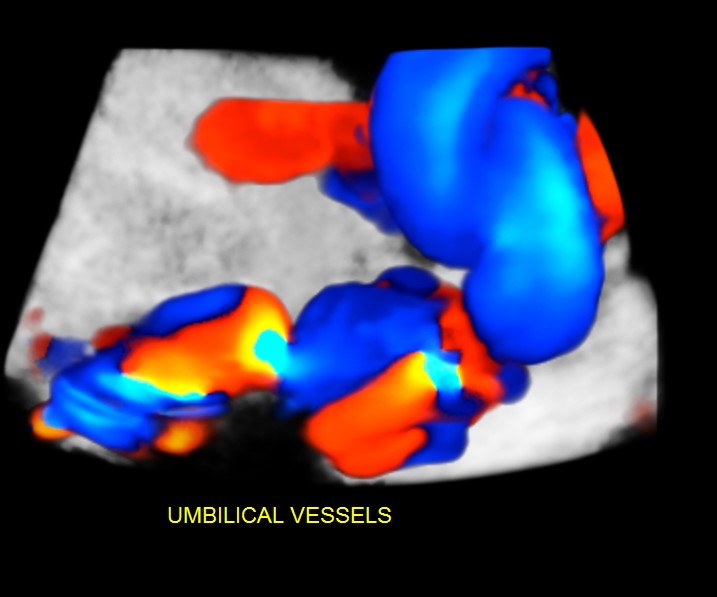

The scan was done around the 35 weeks.The following images were seen .

An umbilical varix is a developmental rather an embryologic abnormality and most cases have a normal ultrasound at 16 to 19 weeks gestation.

Unlike persistent right umbilical vein, umbilical vein varices have not been associated with other congenital malformations.

The significance of an antenatally detected umbilical varix remains controversial.

This finding has been associated with an unexplained high mortality rate in utero: thrombosis of the dilation leading to fetal death and other complications including hydrops fetalis. It had also been linked with chromosomal abnormalities.